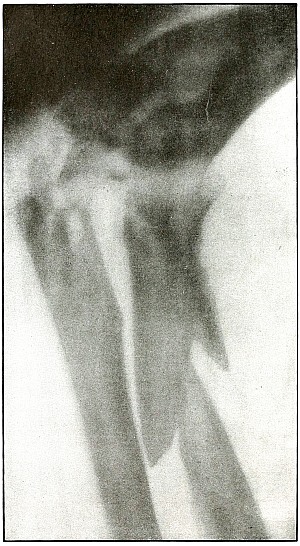

Plate 57.

[Pg 125]

Rifle—Plate 57.

LOWER EXTREMITY.

Gunshot Fracture About the Middle of the Femur,

with Lodgment of the Fragments of a Deformed Bullet.

The course of the missile was transverse. All of the remaining energy

of the retarded velocity of the short range of a ricochet shot was

stopped by the bone with the result of a long splitting fracture, and

the lodgment of one large and a few small fragments of the missile.

The small notched metal fragment lying to the right of the upper

bone fragment is a small bent piece of the jacket, detached from the

greatly deformed lead core, which can be faintly seen lying behind the

lower end of the left side of the upper bone fragment.

The treatment is extension with lateral compression, although this